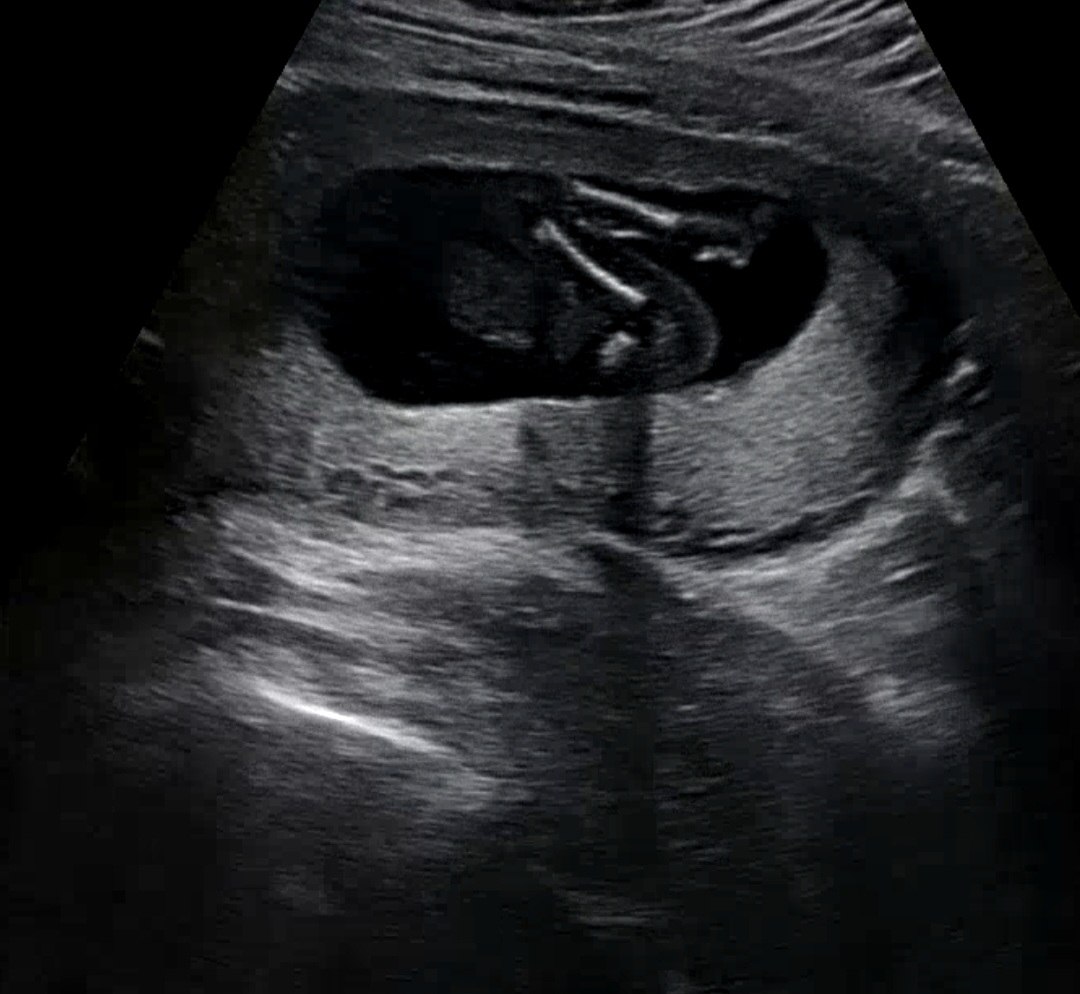

16w 허벅지랑 종아리뼈 인증샷ㅋㅋ

뼈가 너무 선명하게 보여서 신기해요 ㅋㅋ 엉덩이랑 발도 살짝 보이고요 ㅎ 다른분들처럼 가랑이?를 안보여줘서 이렇게 옆으로 누워있는 모습만 보고왔는데 이거 보고 의사쌤은 딸이네요~ 하시더라구요. 반전 가능성 있을까요? 😅😅